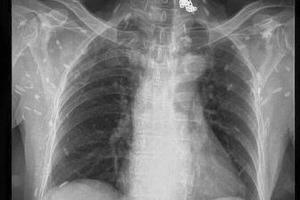

Mấy ngày gần đây, cộng đồng mạng chia sẻ các bức ảnh chụp X-quang rất khủng khiếp của một bệnh nhân nhiễm sán. Theo đó, trên các bức ảnh X-quang là la liệt các xác sán xơ mít có đầu vôi hóa hình như hạt gạo. Theo các bác sĩ, nguyên nhân bị nhiễm sán là do ăn phải thức ăn sống như rau sống, tiết canh, gỏi cá… có nhiễm trứng, ấu trùng sán.